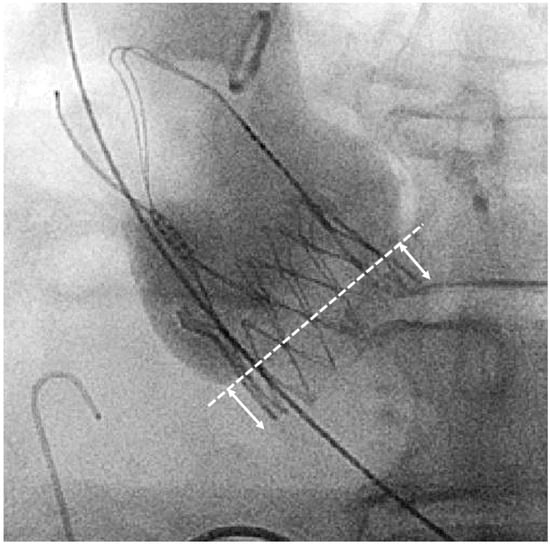

2.4. Definition and Measurement of Implantation Depth